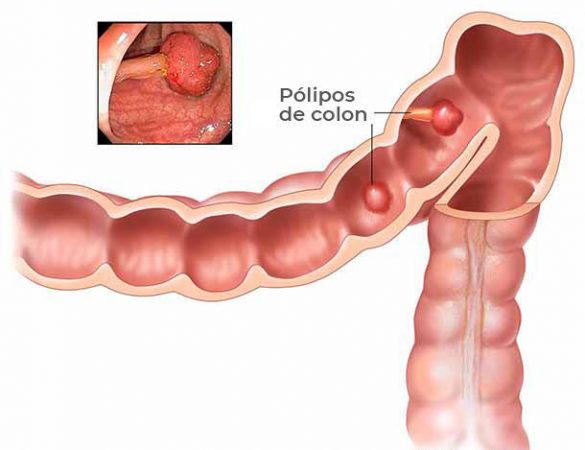

- Antecedentes personales de pólipos de colon, enfermedad de Crohn, Colitis Ulcerativa Crónica Inespecífica (CUCI) o haber padecido otro cáncer con anterioridad (mama, ovario, endometrio y colon)

- Tener 1 familiar de primer grado (padres, hijos o hermanos) o 2 familiares de segundo grado (tíos, primos, abuelos) con cáncer de colon o pólipos de colon.

Si. TODAS LA PERSONAS se deben hacer el estudio de COLONOSCOPIA a los 50 años AUNQUE NO TENGAN NINGUN FACTOR DE RIESGO aparte de la edad. Esto es porque de cada 10 pacientes que tienen Cáncer de Colon, 9 de ellos NO TENIAN NINGUN ANTECEDENTE DE CÁNCER EN LA FAMILIA.

Debe acudir lo más pronto posible con un médico general o un coloproctólogo a fin de establecer un plan personal de detección temprana de lesiones pre-cancerosas (que se pueden volver cáncer al paso del tiempo). Hay muchos estudios, pero lo más frecuente es que se realicen al menos dos estudios: Detección de sangre oculta en materia fecal y Colonoscopía. Le recordamos que TODAS LAS PERSONAS se deben hacer el estudio de COLONOSCOPIA a los 50 AÑOS aunque no tenga factores de riesgo; sin embargo, no olvide que su médico, de acuerdo a su caso y antecedentes, le indicará si la colonoscopía se debe hacer antes o si requiere otros estudios complementarios, así como cada cuanto tiempo se deben repetir.

Existen diversos tratamientos que se indican de acuerdo al caso. En caso de encontrar lesiones pre-cancerosas se pueden retirar en el mismo momento de la colonoscopía o mediante cirugía. En caso de que se trate de cáncer, se realizar cirugía, radioterapia, quimioterapia, o una combinación de éstas de acuerdo al caso. Su médico le podrá indicar el tratamiento exacto después de valorarlo.